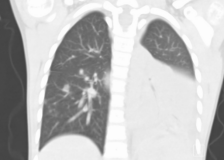

重症肺炎支原体肺炎,可出现呼吸困难、胸痛、咯血等表现。肺部CT可见:塑形性支气管炎、胸腔积液、肺实变和坏死、肺栓塞等表现(如下图)

③影像学表现实变胸腔积液